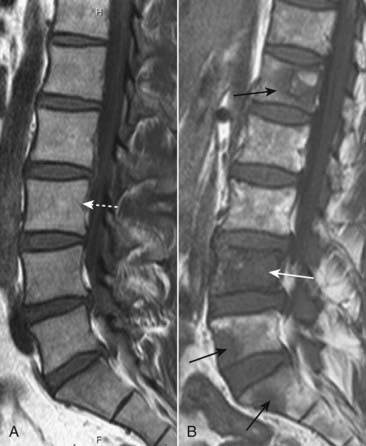

image MRI, on the other hand, is excellent at demonstrating the status of the medullary cavity and so is much more sensitive to the presence of metastatic disease than conventional radiography (Fig. 21-19).

image

Figure 21-19 Metastases to lumbar spine, MRI.

A, There is normal signal in the lumbar vertebral bodies on this T1-weighted sagittal view of the lumbar spine (dotted white arrow). B, In this patient with a primary breast carcinoma, there are multiple metastatic deposits replacing the normal marrow in the lumbar spine and sacrum (solid black arrows). The body of L4 is completely replaced by tumor (solid white arrow).